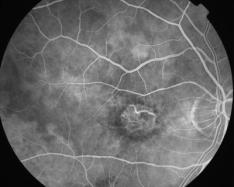

ATROPHIE AREOLAIRE CENTRALE

IMG0006.jpg